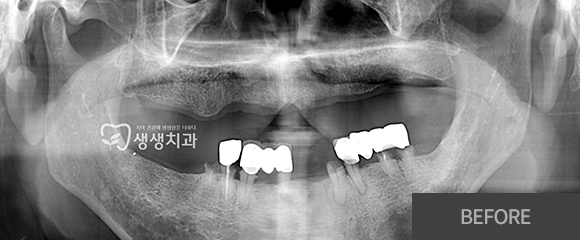

전악(전체) 임플란트

CASE 2